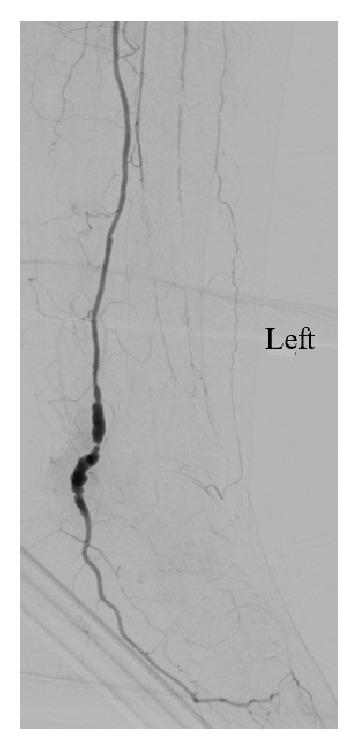

True aneurysms of the tibial arteries are extremely rare. Of the few previously described tibial artery aneurysms, there are scant reports of isolated true aneurysms of the posterior tibial artery (PTA). In this report, we describe the second documented case of bilateral true PTA aneurysms. Unique aspects of this case are that the aneurysmal PTA were the only patent tibial arteries bilaterally, the aneurysms were degenerative in nature, and initial patient presentation was due to aneurysm thrombosis causing acute foot ischemia. The clinical and radiological features of this case, as well as surgical decision making and management, are discussed.

胫动脉真性动脉瘤极为罕见。在先前描述的少数胫动脉动脉瘤中,关于孤立性胫后动脉(PTA)真性动脉瘤的报道极少。在本报告中,我们描述了第二例有文献记载的双侧PTA真性动脉瘤病例。该病例的独特之处在于,双侧动脉瘤性PTA是仅存的通畅胫动脉,动脉瘤为退行性病变,且患者最初的表现是由于动脉瘤血栓形成导致急性足部缺血。本文讨论了该病例的临床和影像学特征,以及手术决策和治疗方法。